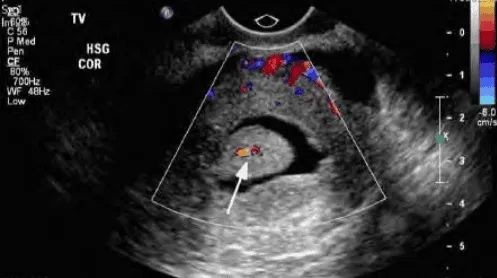

Doppler: Mạch ngoại vi u xơ; Phân biệt với polyp (mạch trung tâm) và adenomyosis (mạch nội vi).

Hình ảnh “Phân biệt polyp và u xơ tử cung FIGO 1 bằng Doppler”.